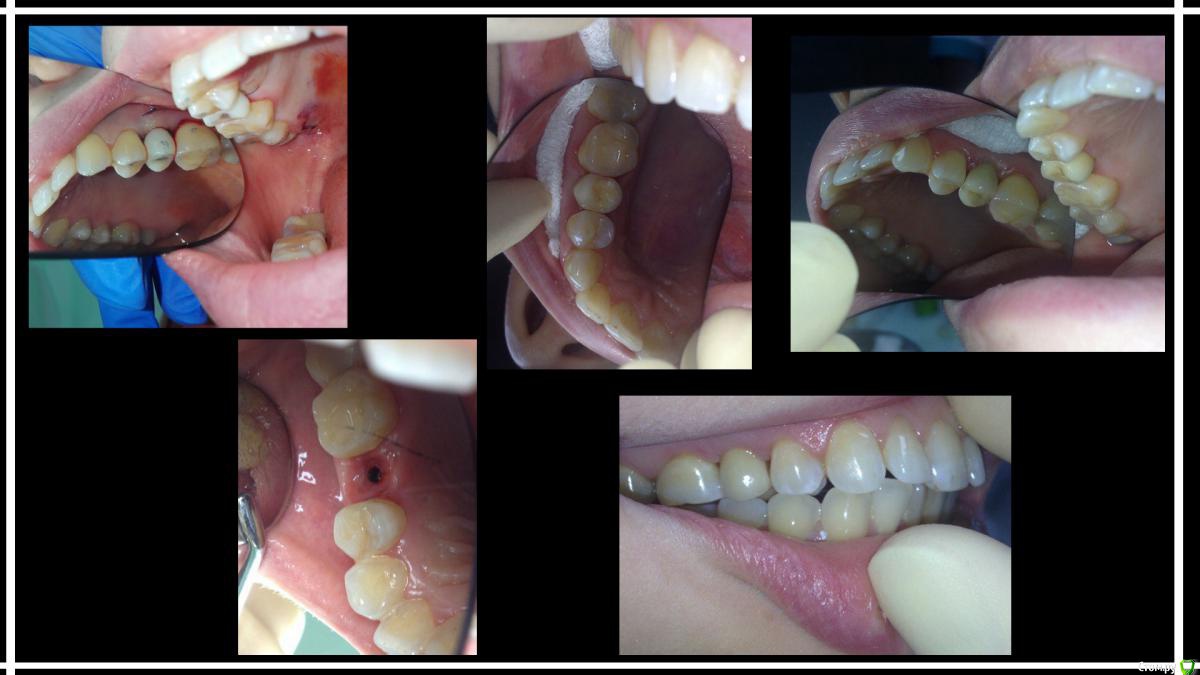

karasov Опубликовано 21 ноября, 2016 Поделиться Опубликовано 21 ноября, 2016 Удален 15, через пару месяцев osstem 3.5-10 ,тк торка не было-заглушка,ушивание. Еще 3 мес, времяшка+сст. Ну и протезирование 7 Ссылка на комментарий

Nazim_NV86 Опубликовано 21 ноября, 2016 Поделиться Опубликовано 21 ноября, 2016 Это временный абатмент подпиленный? Ссылка на комментарий

karasov Опубликовано 21 ноября, 2016 Автор Поделиться Опубликовано 21 ноября, 2016 Это временный абатмент подпиленный?Да. Временный титановый Ссылка на комментарий